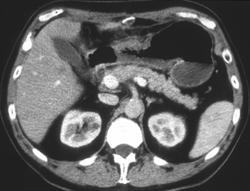

Recurrent Gastric Cancer in Mesenteric Nodes